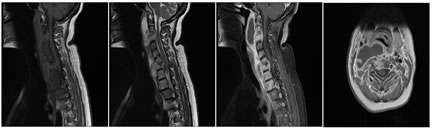

A: SAGITTAL T1W; BSAGITTAL T2W; C: SAGITTAL  T1 CONTRAST FAT SAT; D: AXIAL T1 CONTRAST

Figure 7: 36 year old female patient presented with neck pain and right hand numbness. Near complete collapse of C2, C% and C6 vertebral bodies seen. Significant marrow edema seen (A,B,C). Two paravertebral abscesses seen. First one is seen to the right of C2 with tiny epidural component (D); Second one is larger and multiloculated in nature with pre and paravertebral abscess more to the right side. Gibbus deformity noted at C6-C7 level. Epidural extension is seen through right C6-C7 neural foramen (skip lesions).